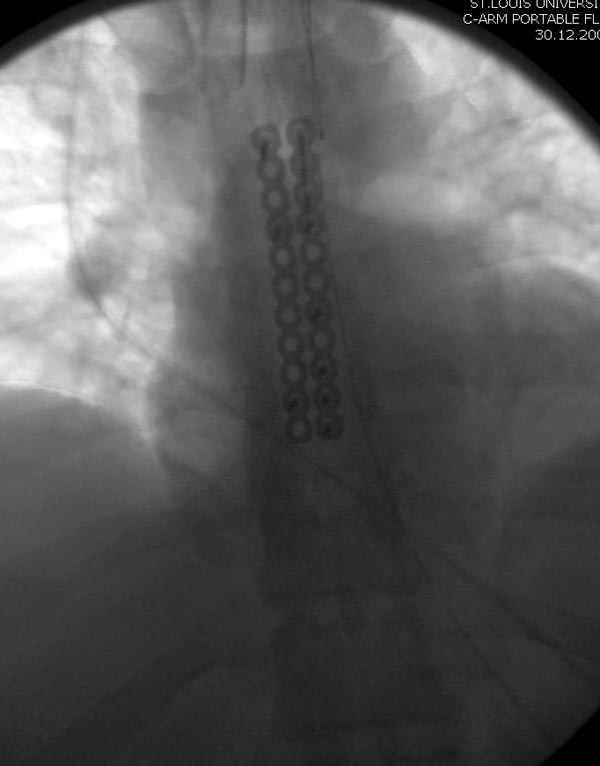

Оперировали вместе с грудным хирургом и в нашем случае главной причиной была болезненность. Во время операции приняли все меры предосторожности недопущения прокола средостения (см. на 4 снимке близкий контур сердца!!)

Ложный сустав зафиксирован двумя пластинами 2.4 мм (locking plate) позаимствованными из челюстно-лицевой хирургии, с костной пластикой, все остальные пластины мне показались слишком толстыми, грубые для грудины или отсутсвовали возможности создания угловой стабильности.

Рентген снимки во время операции и последние сделаны на днях.